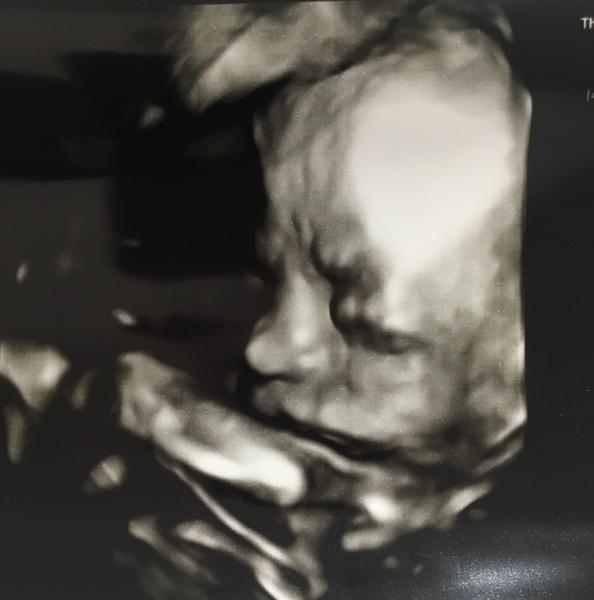

@heregova jeej,viem sI to predstavit,aj mne stale tisne slzicky ked vidim moju babu na sone...Blahozelam,hlavne vela zdravicka❤👶

@janinamojka dakujem,aj vam obom len to najlepsie❤️